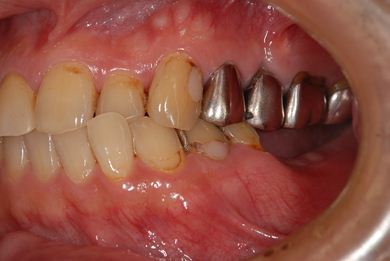

| 性別/年齢 | 男性 / 53歳 | ||||||||||||||||||||||||||||||||

| 主訴 | 左下奥歯2本のインプラント治療を希望。 | ||||||||||||||||||||||||||||||||

| 治療方針 | 左下欠損部分をインプラント治療にて機能的・審美的回復を行う。 | ||||||||||||||||||||||||||||||||

| 治療内容 | インプラント2本、ハイブリッドセラミッククラウン2本 | ||||||||||||||||||||||||||||||||

| 総治療費 | 399,000円 | ||||||||||||||||||||||||||||||||

| 治療期間 | 9ヶ月 |